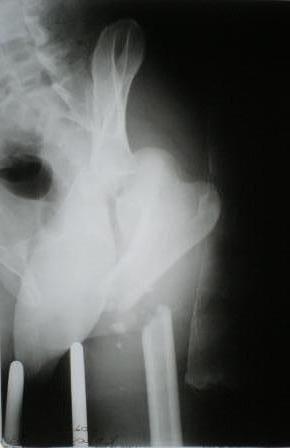

Уважаемые коллеги! Помогите пожалуйста в лечении сложного клинического случая Пациент 33 лет поступил 1.02.08 с диагнозом: Множественная травма. Т-образный перелом свода, перелом заднего края правой вертлужной впадины. Поперечный подвертельный перелом диафиза, подвздошный вывих правого бедра. Поперечный подвертельный перелом диафиза на фоне консолидированного косого перелома в\3 левого бедра в порочном положении. Открытый краевой перелом надколенника правого коленного сустава. Открытый оскольчатый перелом н\челюсти. Закрытый неосложненный перелом V ребра справа. В настоящее время больной компенсирован. Планируем: в положении больного на спине выполнить БИОС левого бедра ретроградно. После повернуть на левый бок и выполнить БИОС правого бедра антеградно одновременно с Y-образным доступом к вертлужной впадине. После - остеосинтез вертлужной впадины реконструктивными пластинами. Посоветуйте пожалуйста: 1. возможно ли выполнить все 3 операции одномоментно? 2. если возможно, то м\б начать операцию на стороне более тяжелого повреждения? Как при этом укладывать, и каким способом оперировать? 3. стоит ли выполнять БИОС левого бедра при условии, что если выбрать штифт длинной до б\вертела, то при введении проксимальный конец пройдет мимо б\вертела по задней поверхности?Заранее благодарен. Гринь Алексей.

Уважаемый доктор,по моему мнению,если то что мы видим на снимках , это настоящее состояние больного,10 дней после травмы, то идет речь о неверно выбранной ,мягко говоря , тактике .

Ваш больной находиться по моему еще перед первой стадией лечения и мне трудно представить ,что он компенсирован ,если его переломы выглядят так , как на снимках , через 10 дней после травмы.

Отдельно можно обсудить тот факт что не вправленная 10 дней головка бедра представит определенную трудность вправлении из за спазма мышц вокруг, а так же очень высокая вероятность некроза головки в будущем .